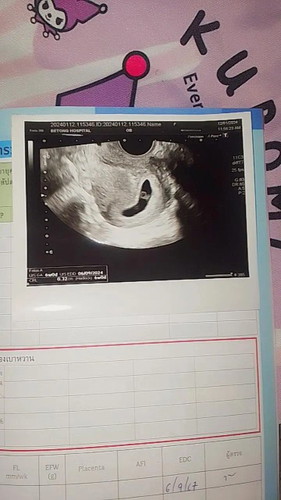

สวัสดีค่ะแม่ๆ วันนี้ไปฝากน้องมา คุณหมอบอก น้อง6week เจอถุงไข่แดงกับหัวใจน้อง แบบนี้จะท้องลมอีกไหมค่ะ

เคยท้องลมเมื่อ3ปีที่แล้ว ขูดมดลูก จนตอนนี้เจ้าตัวเล็กกลับมาแล้ว

เจอถุงไข่แดงไม่ท้องลมแล้วค่ะแม่ ท้องลมจะไม่เจออะไรเลยนอกจากถุงตั้งครรภ์

ซาวด์ทางช่องคลอดค่ะ ซาวด์ทางหน้าท้องไม่เจอค่ะ คุณหมอเลยซาวด์ทางช่องคลอด